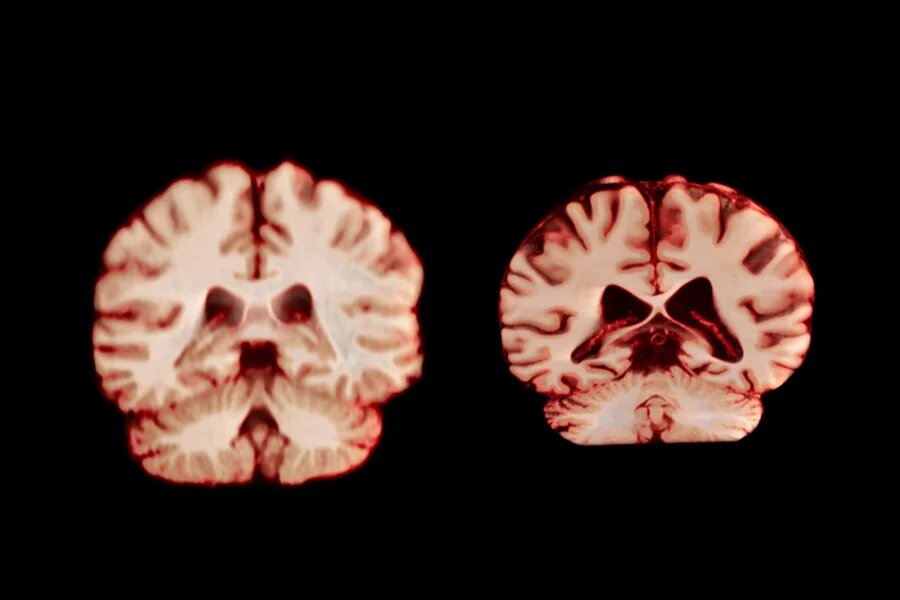

Результаты недавнего исследования, опубликованного в журнале Proceedings of the National Academy of Sciences, показали: с возрастом у мужчин объём мозга уменьшается сильнее и в большем количестве областей, чем у женщин. Это значит, что возраст не объясняет того, почему всё-таки болезнь Альцгеймера у женщин обнаруживают чаще. Болезнь Альцгеймера у женщин диагностируют почти в два раза чаще, чем у мужчин, и возраст - один из факторов риска. Это побудило учёных выяснить, как меняется мозг мужчин и женщин по мере старения. В рамках нового исследования специалисты проанализировали более 12 500 снимков мозга с помощью магнитно-резонансной томографии (МРТ) у 4726 человек. На каждого участника приходилось минимум два снимка, сделанных со средним интервалом в три года. В целом у мужчин наблюдалось более значительное уменьшение объёма в большем количестве областей мозга по сравнению с женщинами. К примеру, постцентральная кора, отвечающая за обработку тактильных, болевых и температурных ощущений

TheVisualMD/Science Source

В целом у мужчин наблюдалось более значительное уменьшение объёма в большем количестве областей мозга по сравнению с женщинами. К примеру, постцентральная кора, отвечающая за обработку тактильных, болевых и температурных ощущений, а также за собственное положение и движения тела, у них сокращалась на 2,0%, тогда как у женщин - на 1,2% в год.